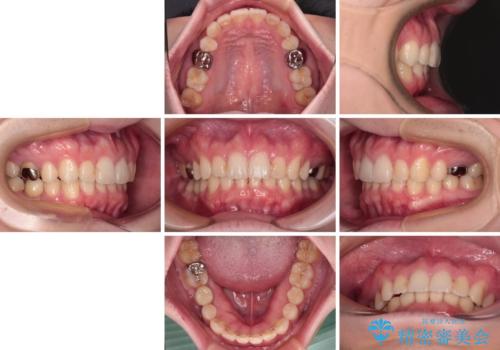

- 咬み合わせと前歯のデコボコを気にして来院された患者様です。

前から5番目の永久歯が3本欠損しており、乳歯が残存している状態でしたが、インビザラインでも十分に対応可能と判断し、インビザラインにて矯正治療を行うこととしました。

今回は部分的にワイヤー矯正を用いましたが、右下の乳歯は全く動かなかったため、抜歯をした上でインプラントを埋入し、オールセラミッククラウンにて補綴治療を行いました。